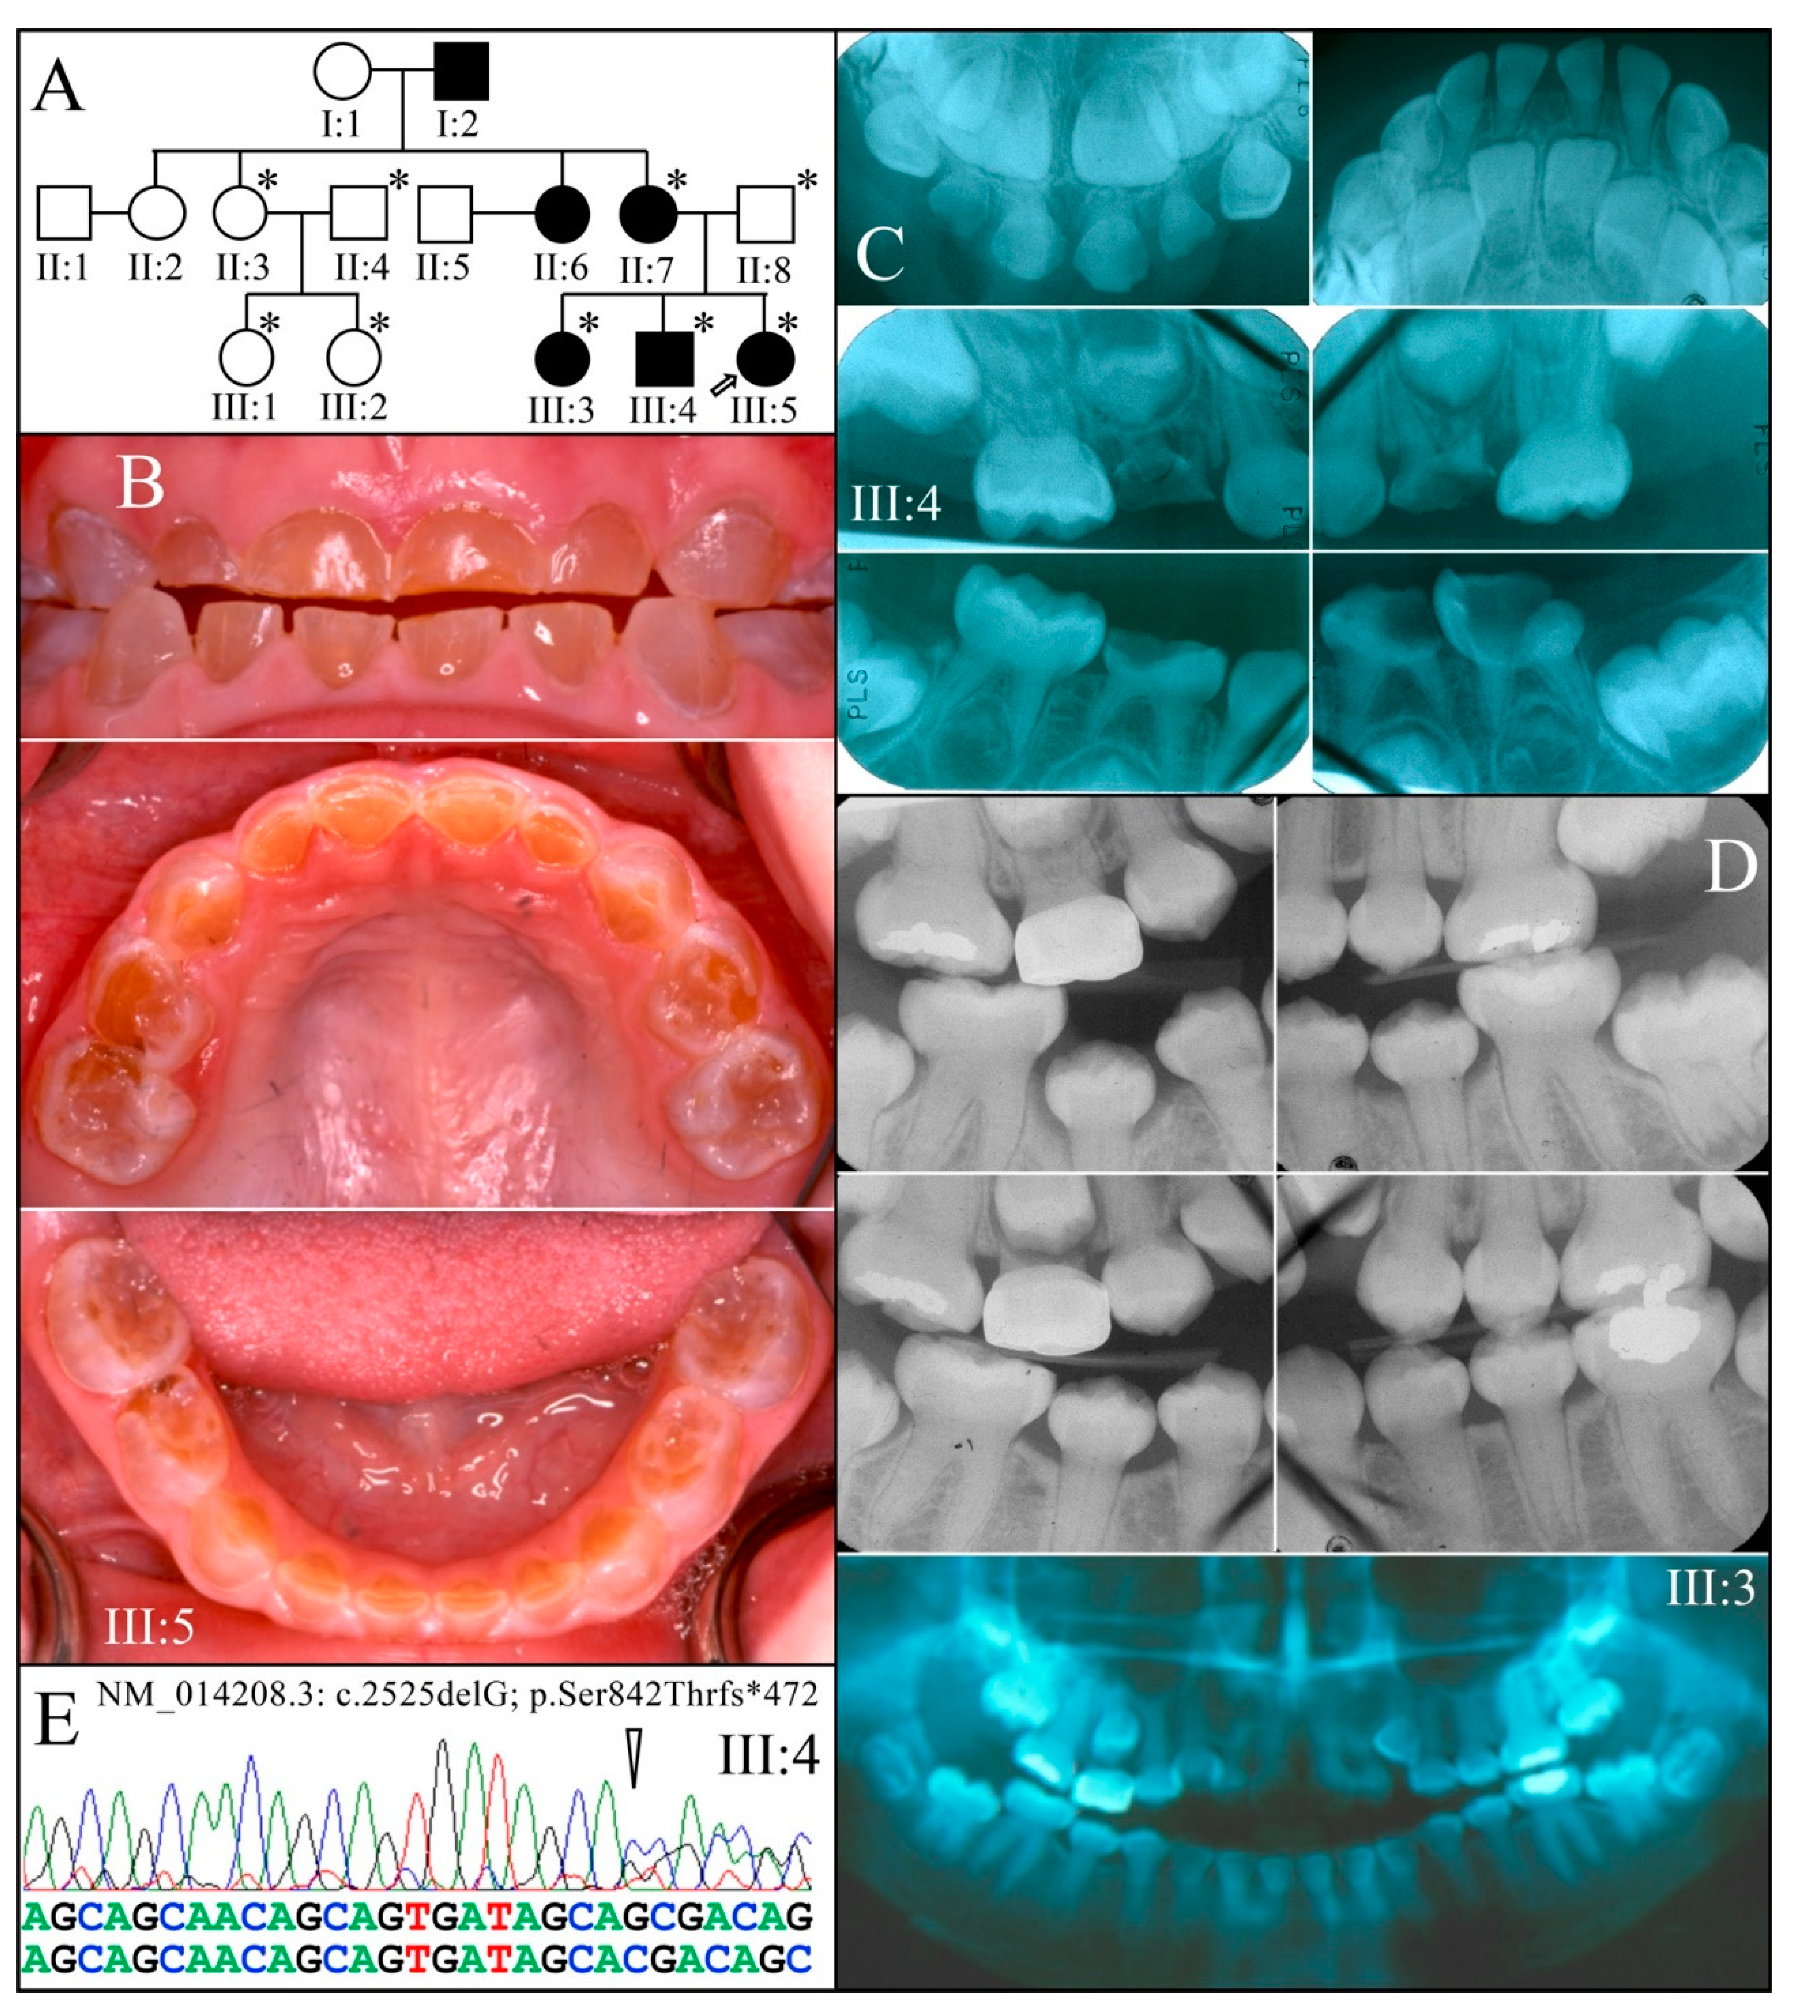

3.2. Four Families with DGI-III: 5′ DSPP Mutations

3.3. Eight Families with 3′ DSPP Mutations Causing DD-II or DGI-II